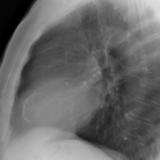

Ao valve calcif (lat only)

Date: 01/26/2009

Views: 2739